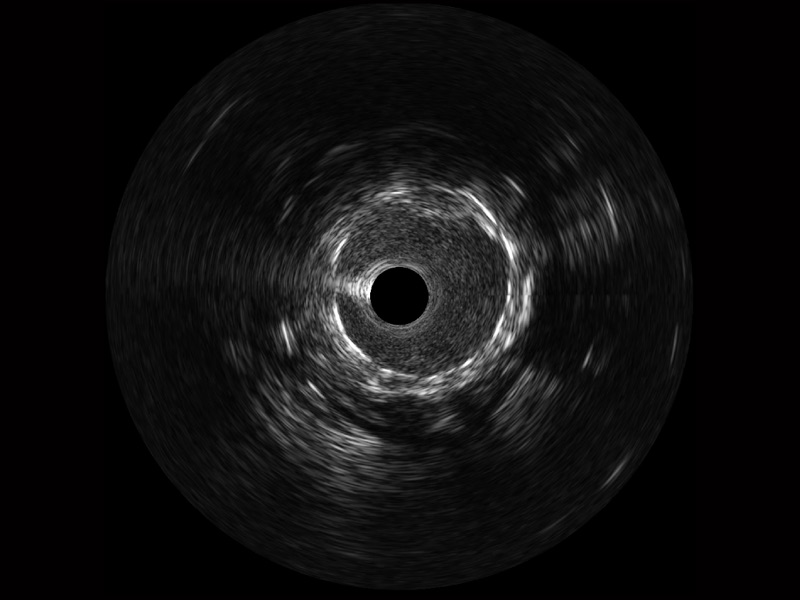

银河优越会宽频IVUS图像

传统IVUS图像

对比传统IVUS导管成像,银河优越会宽频IVUS图像的近场支架梁显影更细腻,远场中膜外血管仍清晰可辨,兼顾远中近,兼顾分辨力与穿透深度